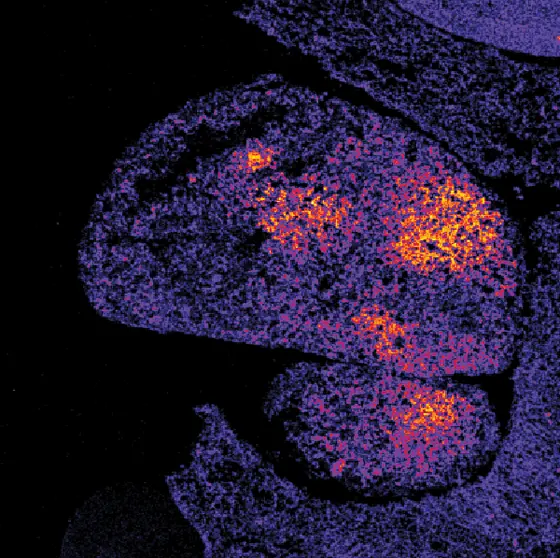

Oxidantienbildung in der Leber – mit einem neuen Biosensor auf einem Gewebeschnitt sichtbar gemacht.

Dieses Problem konnten die DKFZ-Forscher um Tobias Dick nun lösen. Durch eine besondere Kombination aus Kälte und einer chemischen Behandlung konnten sie den Zustand des Biosensors im entnommenen Gewebe sofort dauerhaft konservieren. So ließ sich auf einem fixierten Gewebeschnitt die räumliche Verteilung der Oxidantien sichtbar machen, so wie sie auch der Verteilung im lebenden Organismus entspricht.

Als Beispiele zeigen die Forscher in ihrer Publikation die Verteilung von Oxidantien in einem wachsenden Tumor, die Reaktion der Leber auf eine Entzündung und die Reaktion von Muskelfasern auf Hunger. Mit dem neuen Verfahren wollen die DKFZ-Forscher nun den Einfluss von Krankheiten und Wirkstoffen auf die Verteilung von Oxidantien im ganzen Körper studieren.